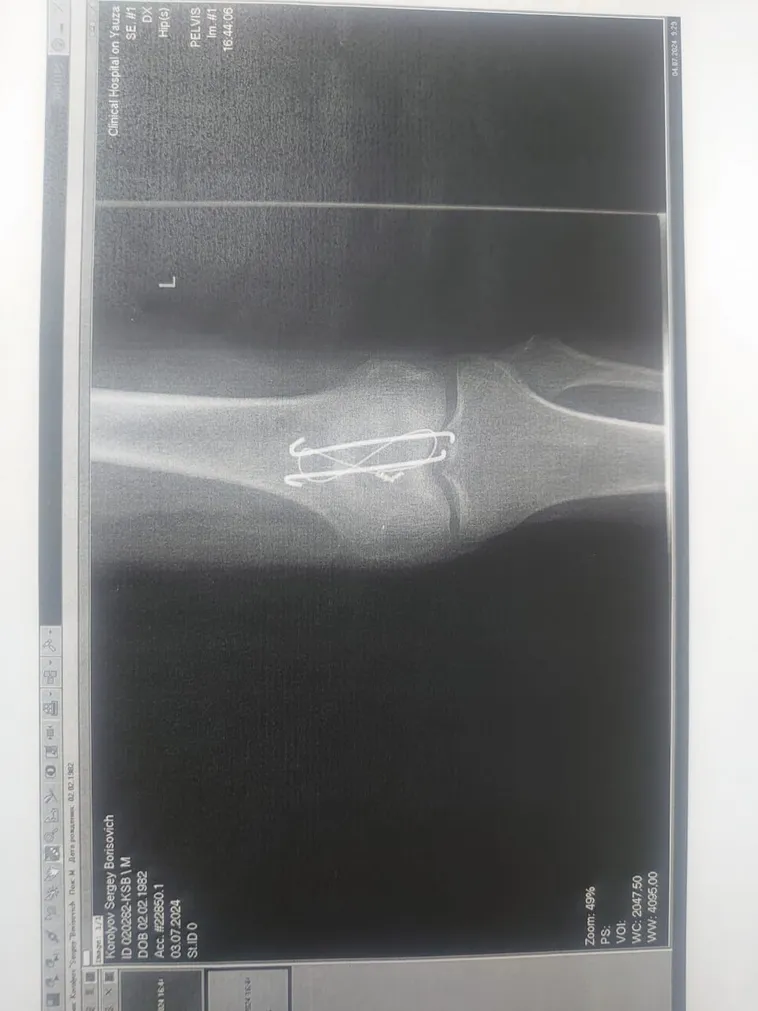

Пример 2 - методика "массаж поющими чашами" в реабилитации после хирургического вмешательства. Постравматическая сгибательная контрактура коленного сустава. Велосипедная травма. Перелом левого надколенника. Проведена операция: остеосинтез надколенника. Провел 5 сеансов по 10 мин, ежедневно. Ногу распрямил полностью. Такие травмы разрабатывается в среднем 2-3 месяца. Комплексное лечение: механотерапия, кинезиотерапия, имплантные препараты и поющая чаша.